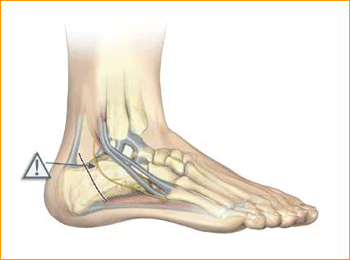

Calcaneal Osteotomy Technique for 6.5 mm Headless Compression screws.

2. APPROACH AND EXPOSURE

An incision is made posterior to the peroneal tendons, perpendicular to the body of the calcaneus. Cephalad and caudal mini Hohman Retractors are

placed to protect the neurovascular structures and plantar fascia. Care is made to preserve the peroneal tendons and the sural nerve.

3. CREATE OSTEOTOMY

An oscillating saw is used to make the osteotomy cut perpendicular to the body of the calcaneus. The saw is not used to complete the cut through the medial cortex. This is completed with an osteotome in order to avoid damaging medial neurovascular structures.

4. GUIDE WIRE PLACEMENT

The body of the calcaneus is displaced medially or laterally and held in place with two guide pins. The distal portion of the pins are placed at the volar aspect of the angle of Gissane in order to capture solid bone distally and assist with compression of the osteotomy by the screws.

Confirm guide pin placement under fluoroscopy.

Tip: The soft tissue protector and arthroscopic probe can be used to assist in guide wire placement.